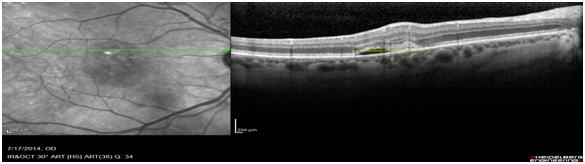

Images of patients (n=63) of patients who had classic type 2 CNV was retrospectively analysed. OCT images obtained on the Heidelberg spectral is at diagnosis were compared to the FFA images obtained on the same day. The OCT biomarker, the sub retinal hyper reflective mass (SRHRM) was used. The same photographer was used to minimise bias. The sub retinal hyper reflective mass was used as the OCT biomarker. The size of this SRHRM was measured at its widest using the caliper setting. This was then compared to the widest diameter of the CNV leakage measured on ultra high-resolution spectral is FFA by drawing a circle around the leage and noting its diameter (Figure 1A,1B & 2A,2B).

Figure 2A Measurement of SRHRM on OCT scans using the caliper measurement (1654m).